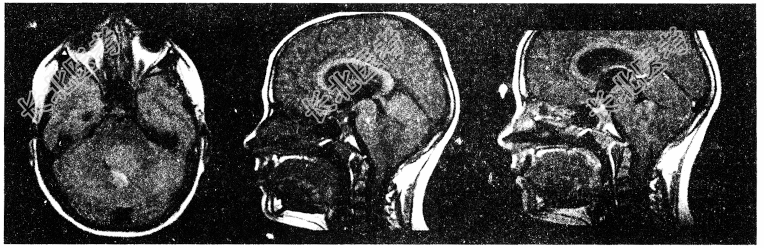

- 单项选择题1.行颅脑MRI检查提示后颅窝占位(如图所示),如患者表现为躯干性和下肢远端共济失调,行走时两足分离过远,左右摇晃呈醉汉步态,病变考虑位于